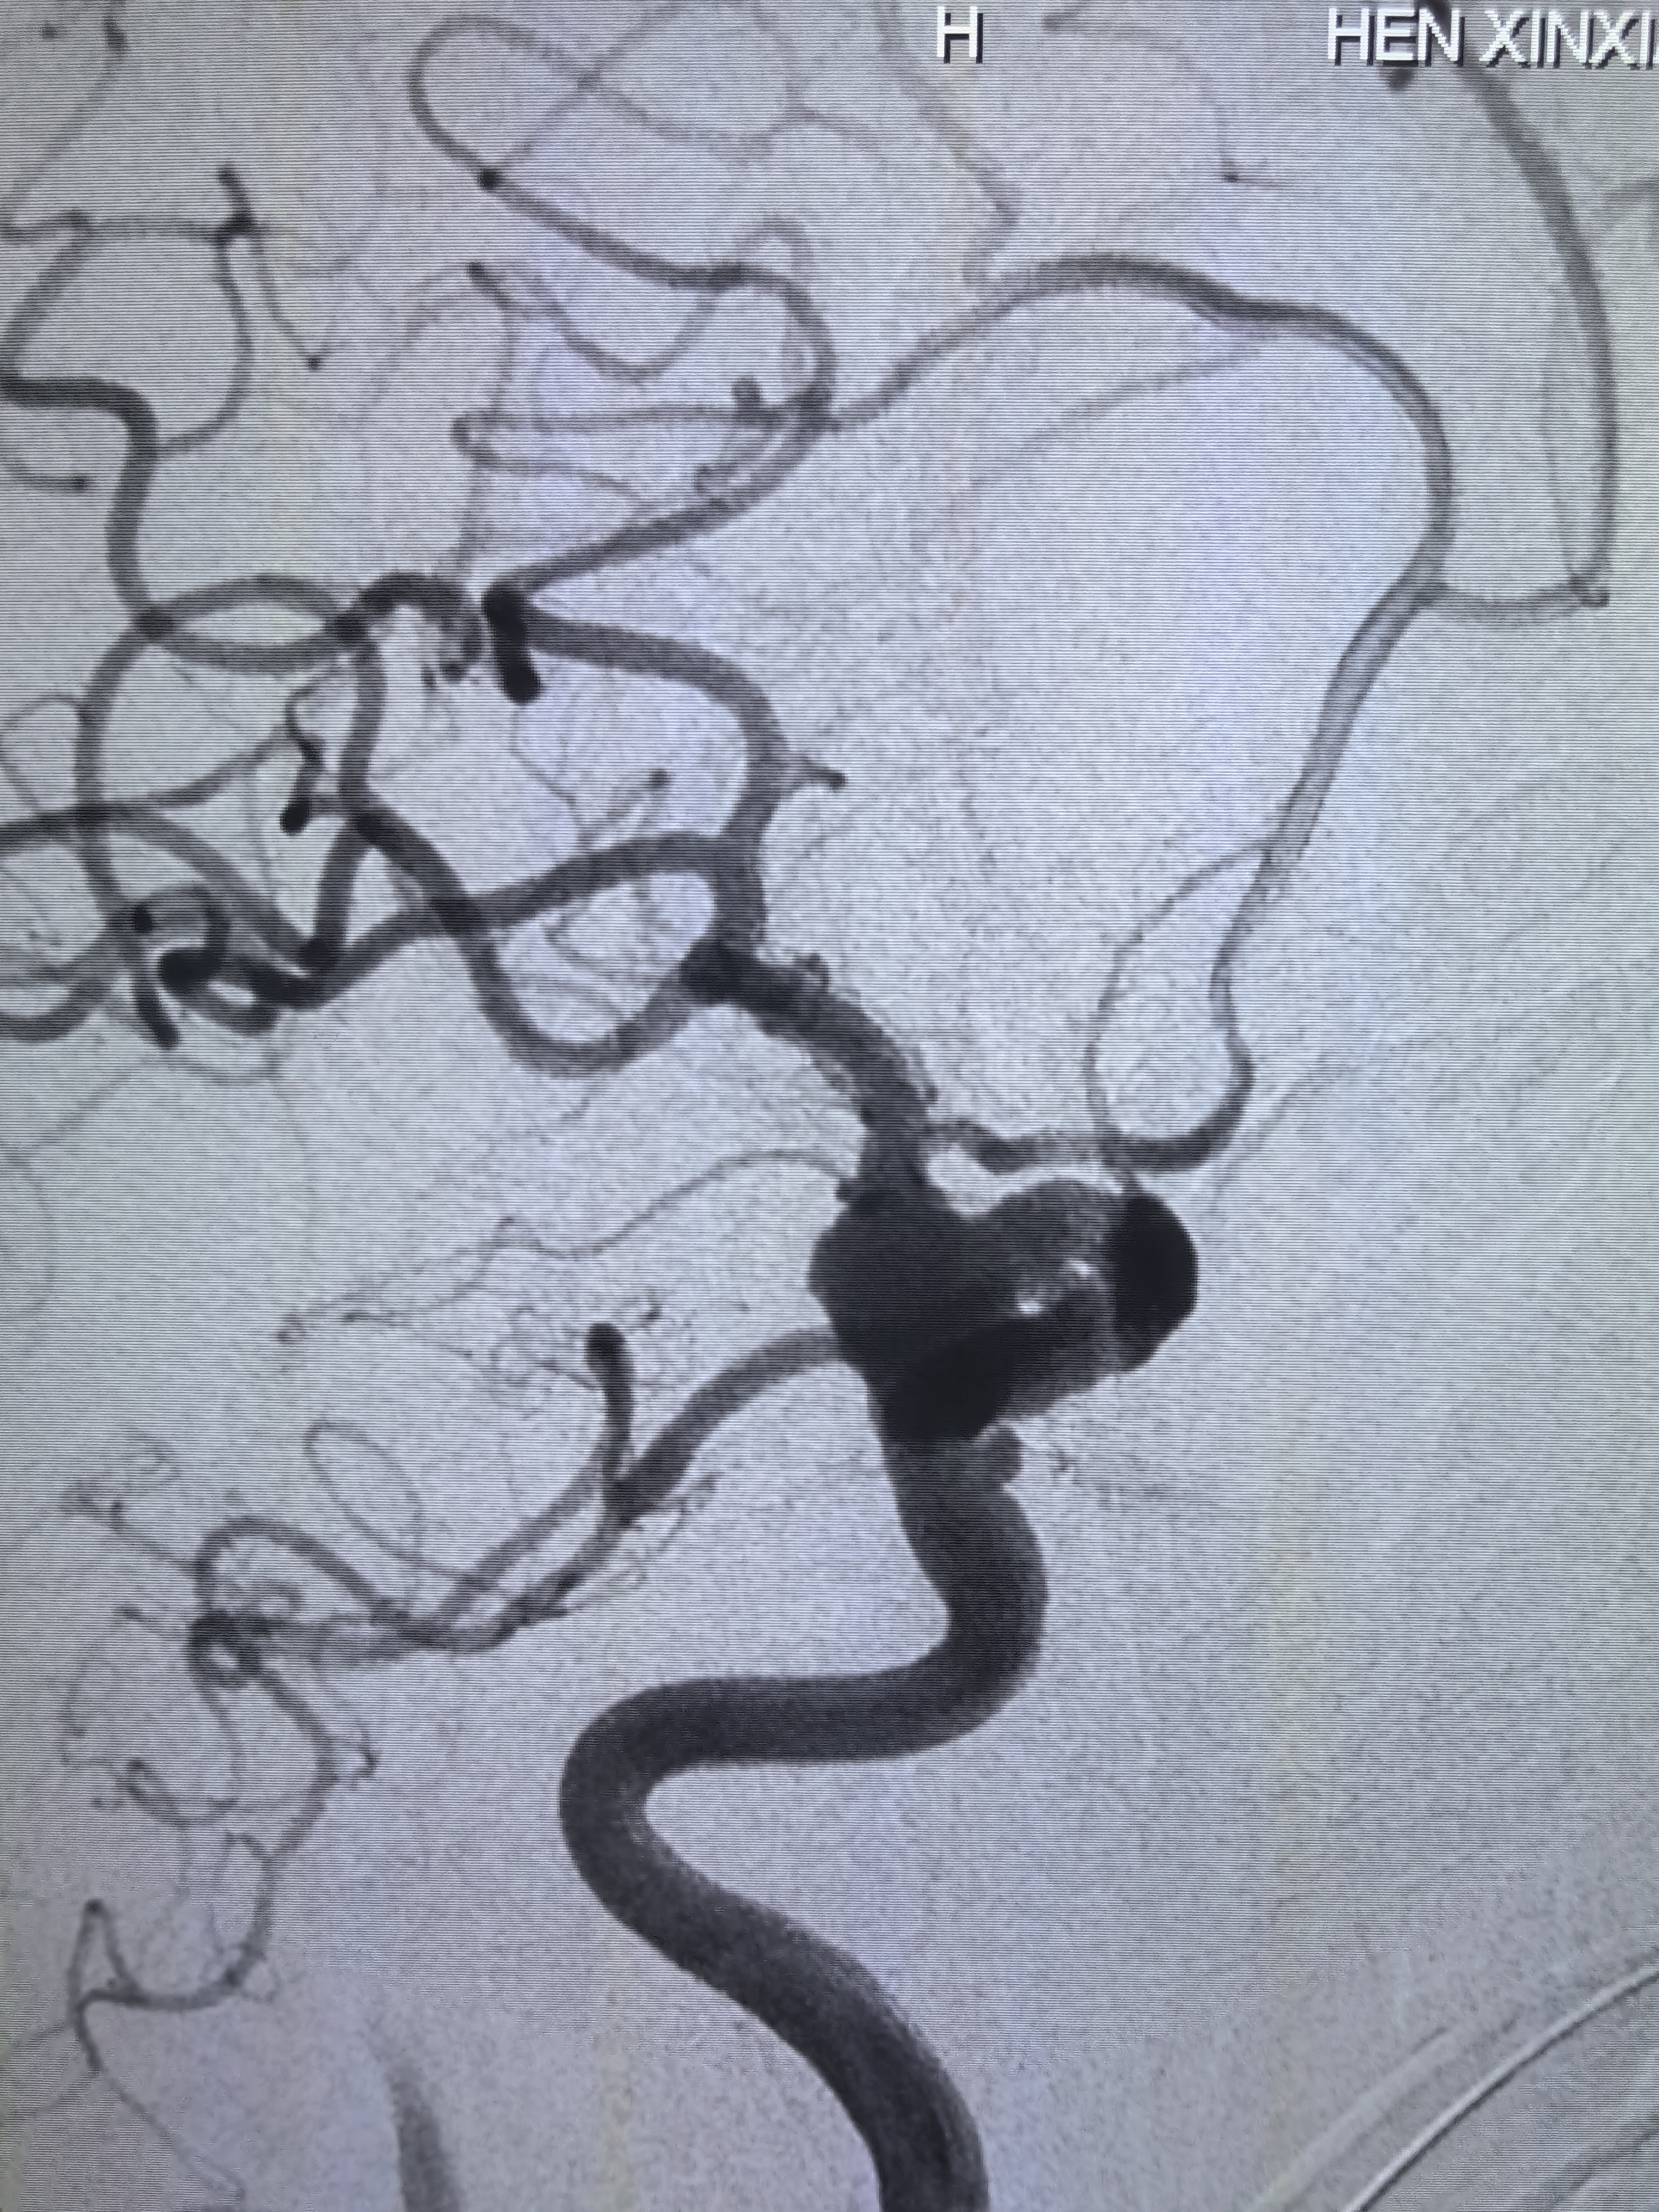

左侧颈内动脉侧位造影!

工作位造影!